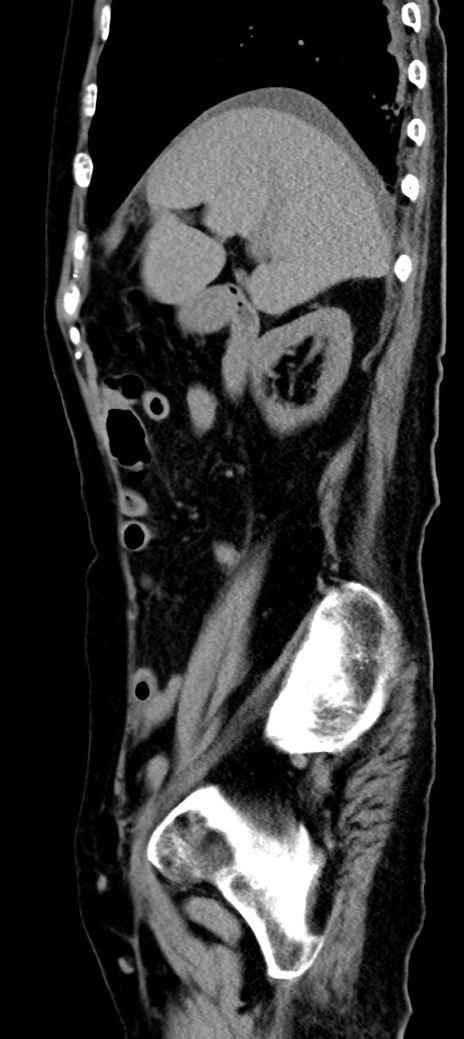

症例40(矢状断像)他院1日前

【症例】90歳代女性

【主訴】腹痛・嘔吐

【現病歴】 食欲低下、嘔吐があり昨日他院受診。肺炎と診断され入院となる。入院後より腹部全体に圧痛あり。胃管留置され経過みていたが、症状持続するため、

当院転院となる。

【既往歴】胸椎圧迫骨折、胆石症

【身体所見】腹部:中央に激痛あり、圧痛あり、反跳痛不明

【データ】WBC 17100、CRP 18.82